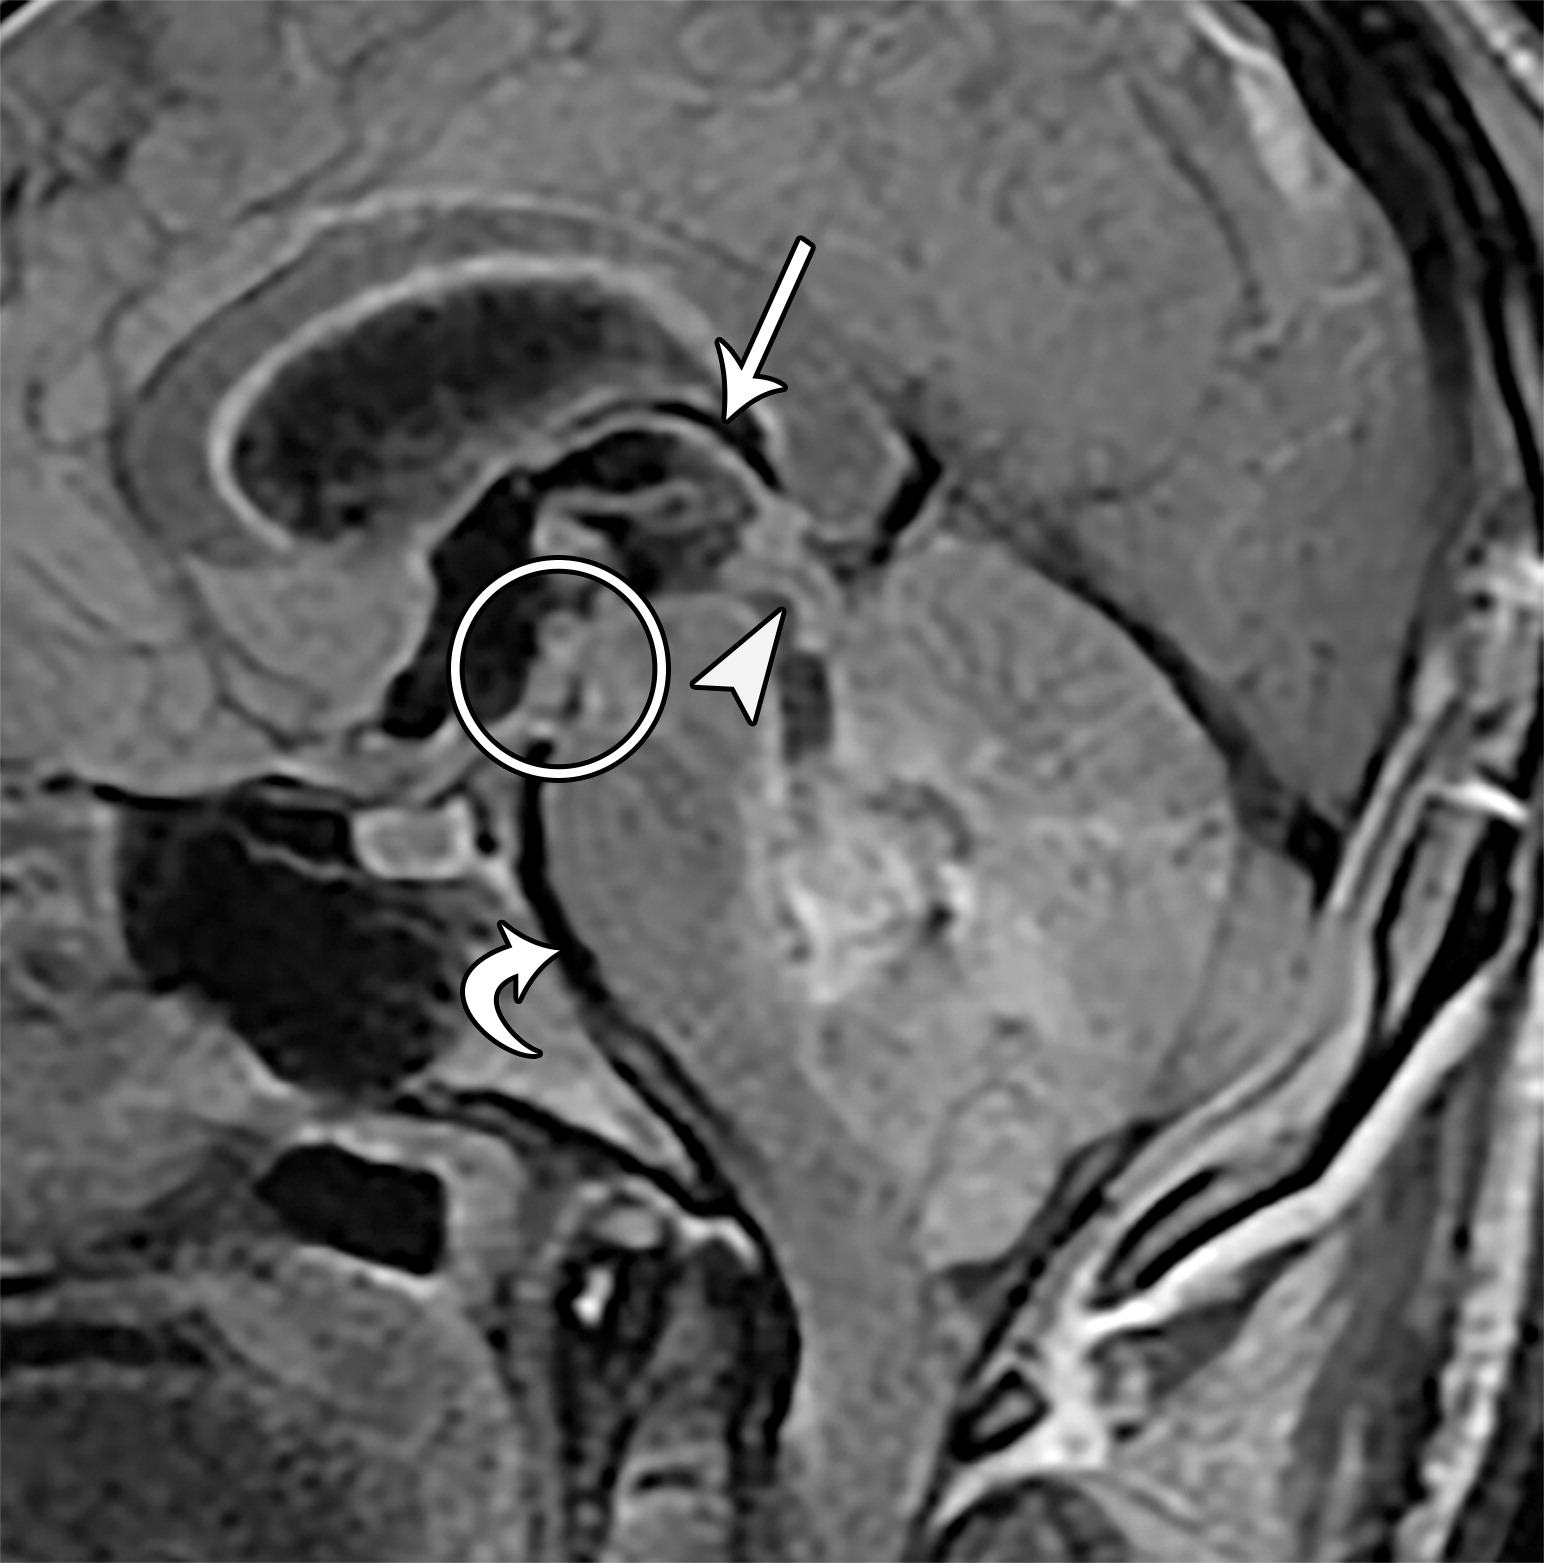

上升性小脑幕裂孔疝。26岁男性,切除髓母细胞瘤后。四叠体池,小脑上池,大脑脚间池的闭塞。下丘(白色短箭头)折叠于上丘的下方,且上丘及下丘两个结构均向上移位。脑干向前移位,导致脑桥池及延髓池间隙变窄(白色弯曲箭头),注意第三脑室顶的向上移位(白色长箭头),乳头体及灰结节向前移位并与中脑紧密相连(白色圆圈)。

4ba8451213c1f99e2e61ef93acd5cfd9.jpeg上升性小脑幕裂孔疝,33岁男性,可疑患有颅内病变。小脑组织(白色*)通过右侧小脑幕切迹(白色短箭头)向上疝出,导致右侧中脑周围池及左侧大脑脚池的闭塞,四叠体池间隙变窄,侧脑室颞角的扩张(黑色*),顶盖及右侧大脑脚(白色长箭头)的水肿。